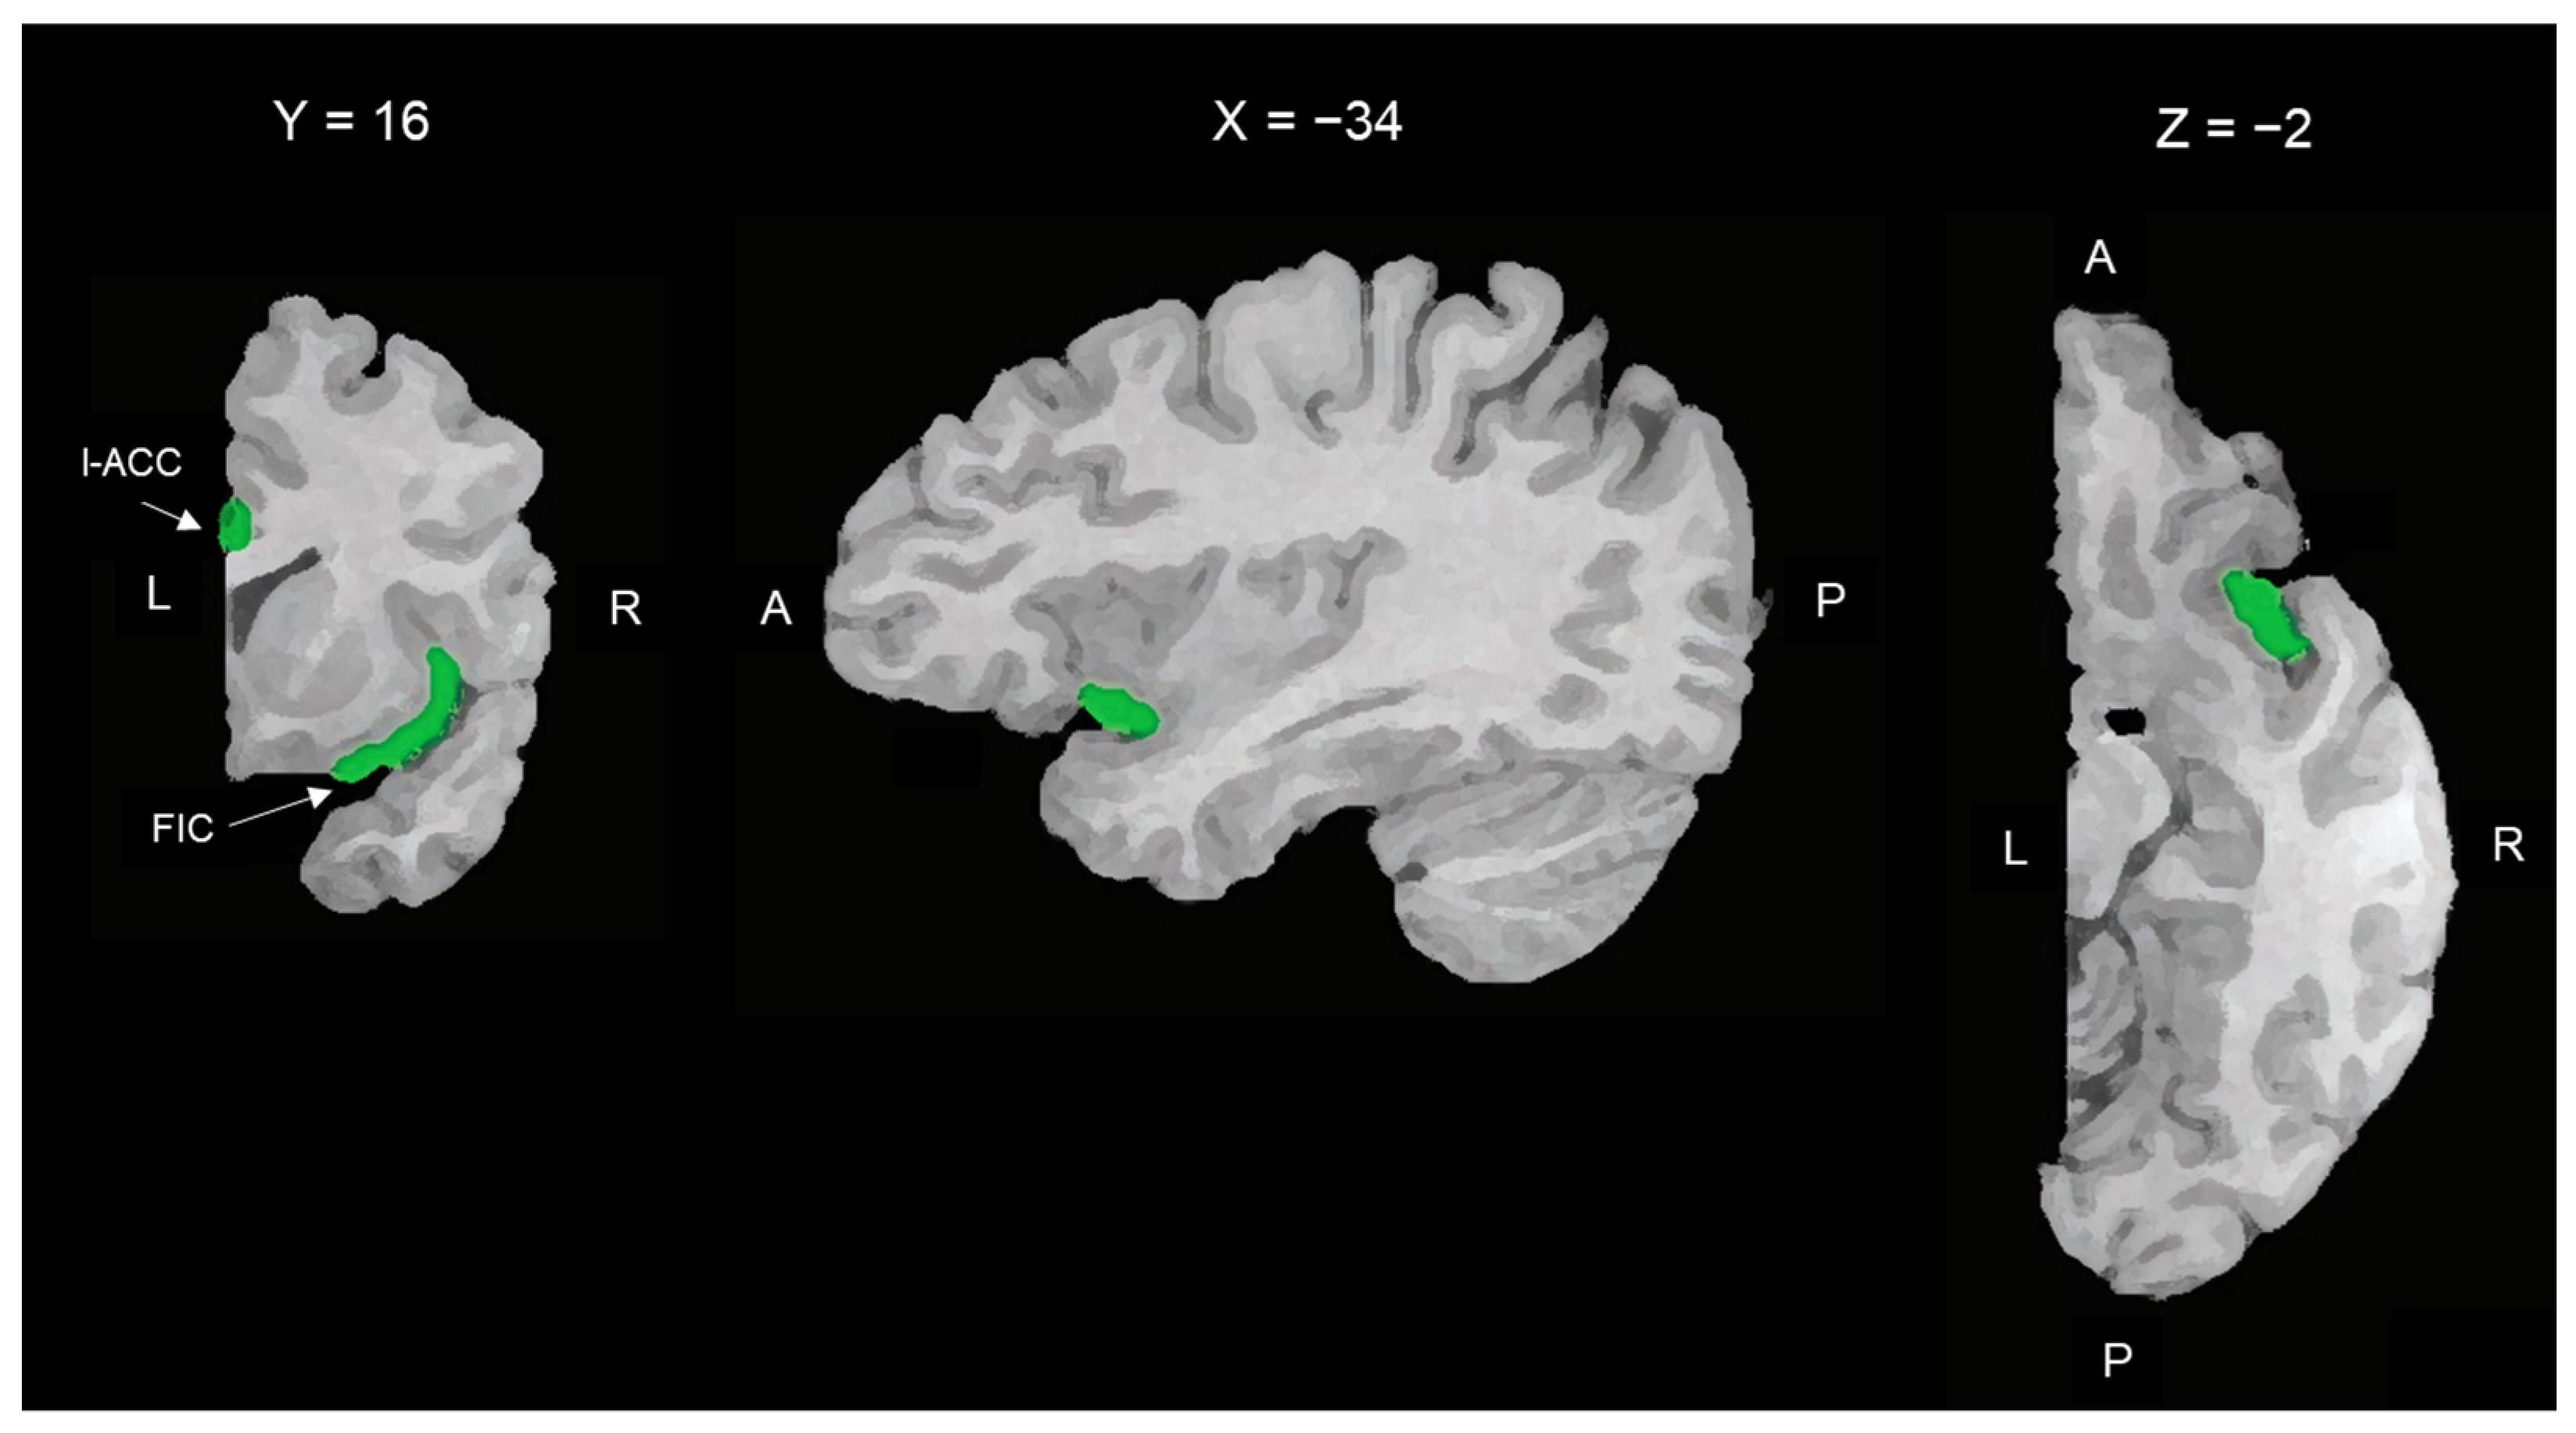

The two ROIs of the right hemisphere are shown in Figure 1.

Figure 1.

Spatial location of the right ROIs used as the seed region for rsFC analysis. From left to right: coronal, parasagittal, and transversal slices of the right hemisphere. ROIs are indicated in green. l-ACC: limbic anterior cortical cortex (Brodmann area 24b); FIC: fronto-insular cortex (anterior short and accessory gyri of the anterior insula). L = left; R = right; A = anterior; P = posterior.